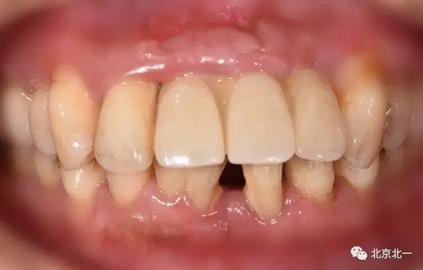

圖六:戴牙后口內(nèi)照,患者笑線低。未做牙齦誘導(dǎo)也不太影響容貌。簡化治療程序節(jié)省患者時間成本以及金錢成本。